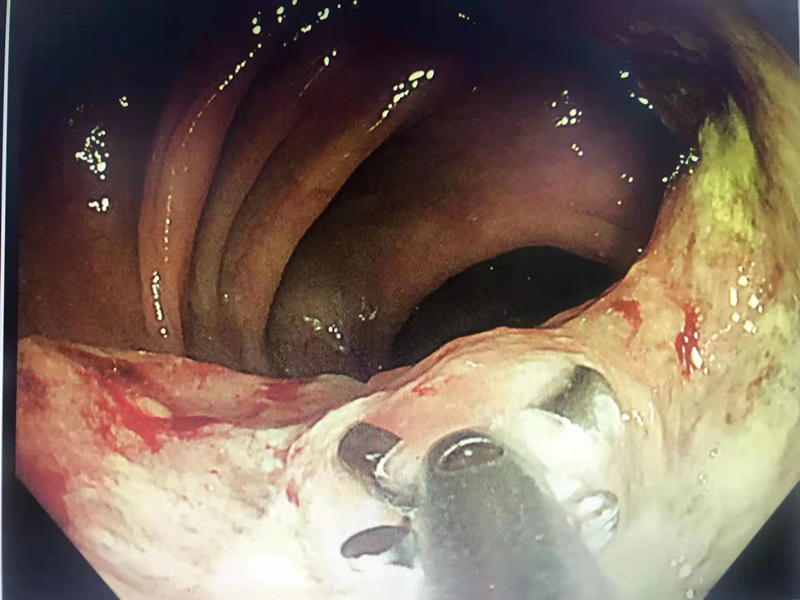

肠镜下直肠肿瘤

肠癌隆起型

直肠癌浸润型

肠癌溃疡型